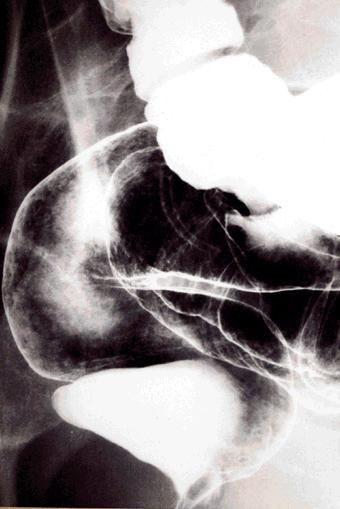

A case of adult T cell leukemia / lymphoma (ATL) of the large intestine.

Tokyo Pref., Cooperative study between National Cancer Center and Kyushu Cancer Center

Malignant Lymphoma/ATL(Adult T-cell Leukemia / Lymphoma)

Large intestine(Colon)/Rectum

X-ray